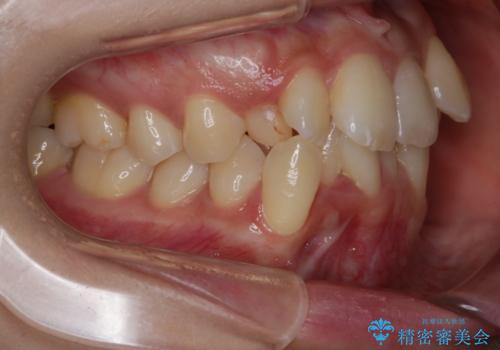

がたつきが強いガチャ歯。埋伏歯抜歯+矯正。すごいところに犬歯が埋まっていたのを抜いてワイヤー矯正治療

がたつきの強さから4本抜歯の必要性がありましたが、右上の歯は犬歯が一本埋まっており、乳歯がある状態でした。

当初、犬歯が動くようであれば代わりに小臼歯を抜歯する予定でしたが、

開窓して器具で力をかけても動く様子がなかったため抜歯とし、小臼歯を犬歯に見立てて治療を完了しました。

今回のように不確定要素がある治療の場合、ワイヤー治療なら臨機応変に対応することが可能となります。